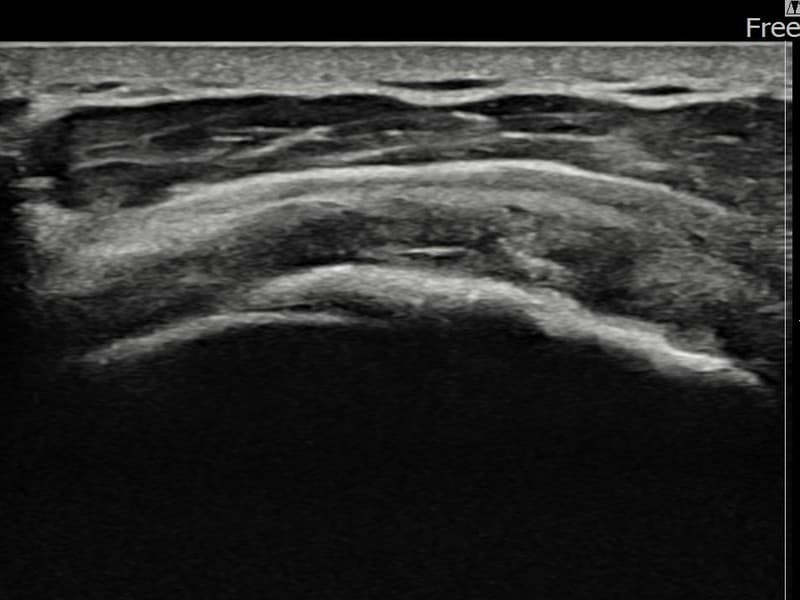

施術後

術前超音波にて左 棘上筋腱 광범위 部分断裂・左肩棘上筋腱のエコー不連続と腱欠損(15mm × 6mm (腱厚の約70%欠損))を確認。術後超音波では断裂部位が再生組織で充填され、腱の連続性回復とエコーパターンの正常化が確認されました。